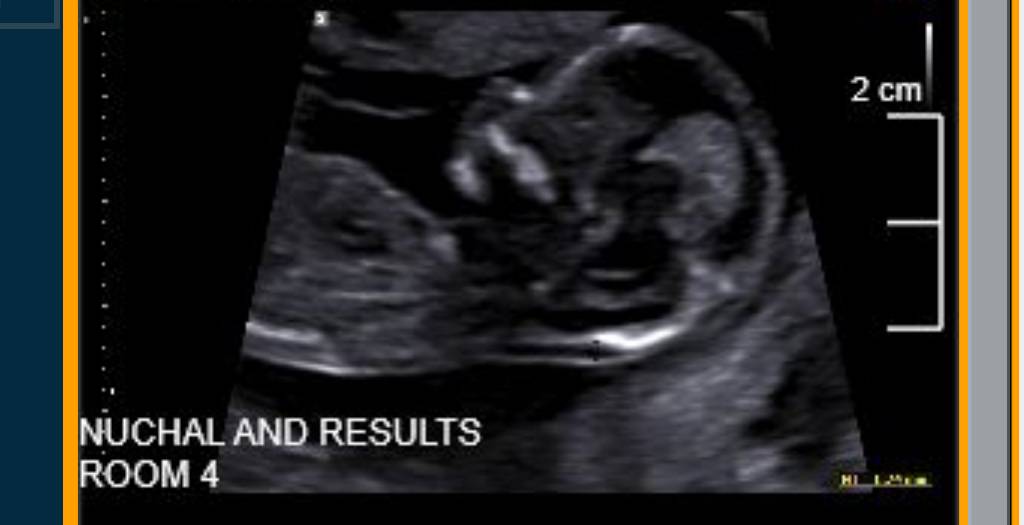

Unfortunately potty shots at 13 weeks aren't reliable and that's why the tech woudln't give an opinion. Do you have any nub shots (taken from the side?)

Looks girly but not greatly reliable at this stage. Mine were accurate though and looked similar to yours and I had a girl.